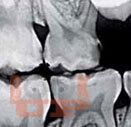

В учебно-методическом пособии рассматриваются основные принципы и методы эндодонтического лечения пульпитов и периодонтитов в детской стоматологической практике. Материал базируется на имеющихся в отечественной и зарубежной литературе современных представлениях по данной проблеме. Издание рекомендуется для использования в основных образовательных профессиональных программах слушателей системы последипломного образования и практической деятельности врачей-стоматологов, клинических ординаторов, аспирантов.